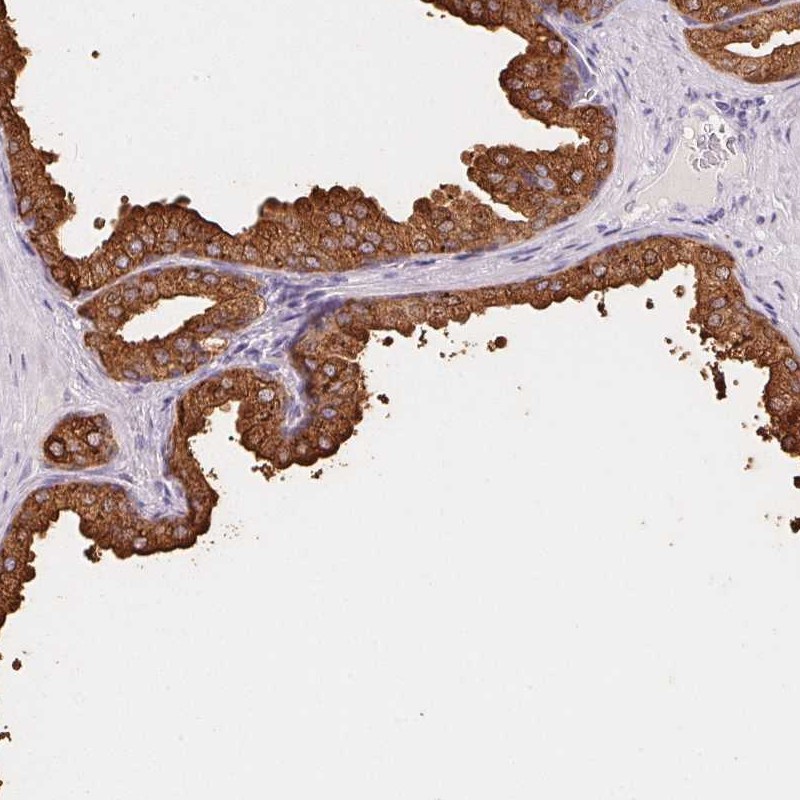

Immunohistochemistry analysis in human prostate and endometrium tissues using Anti-ACPP antibody. Corresponding ACPP RNA-seq data are presented for the same tissues.